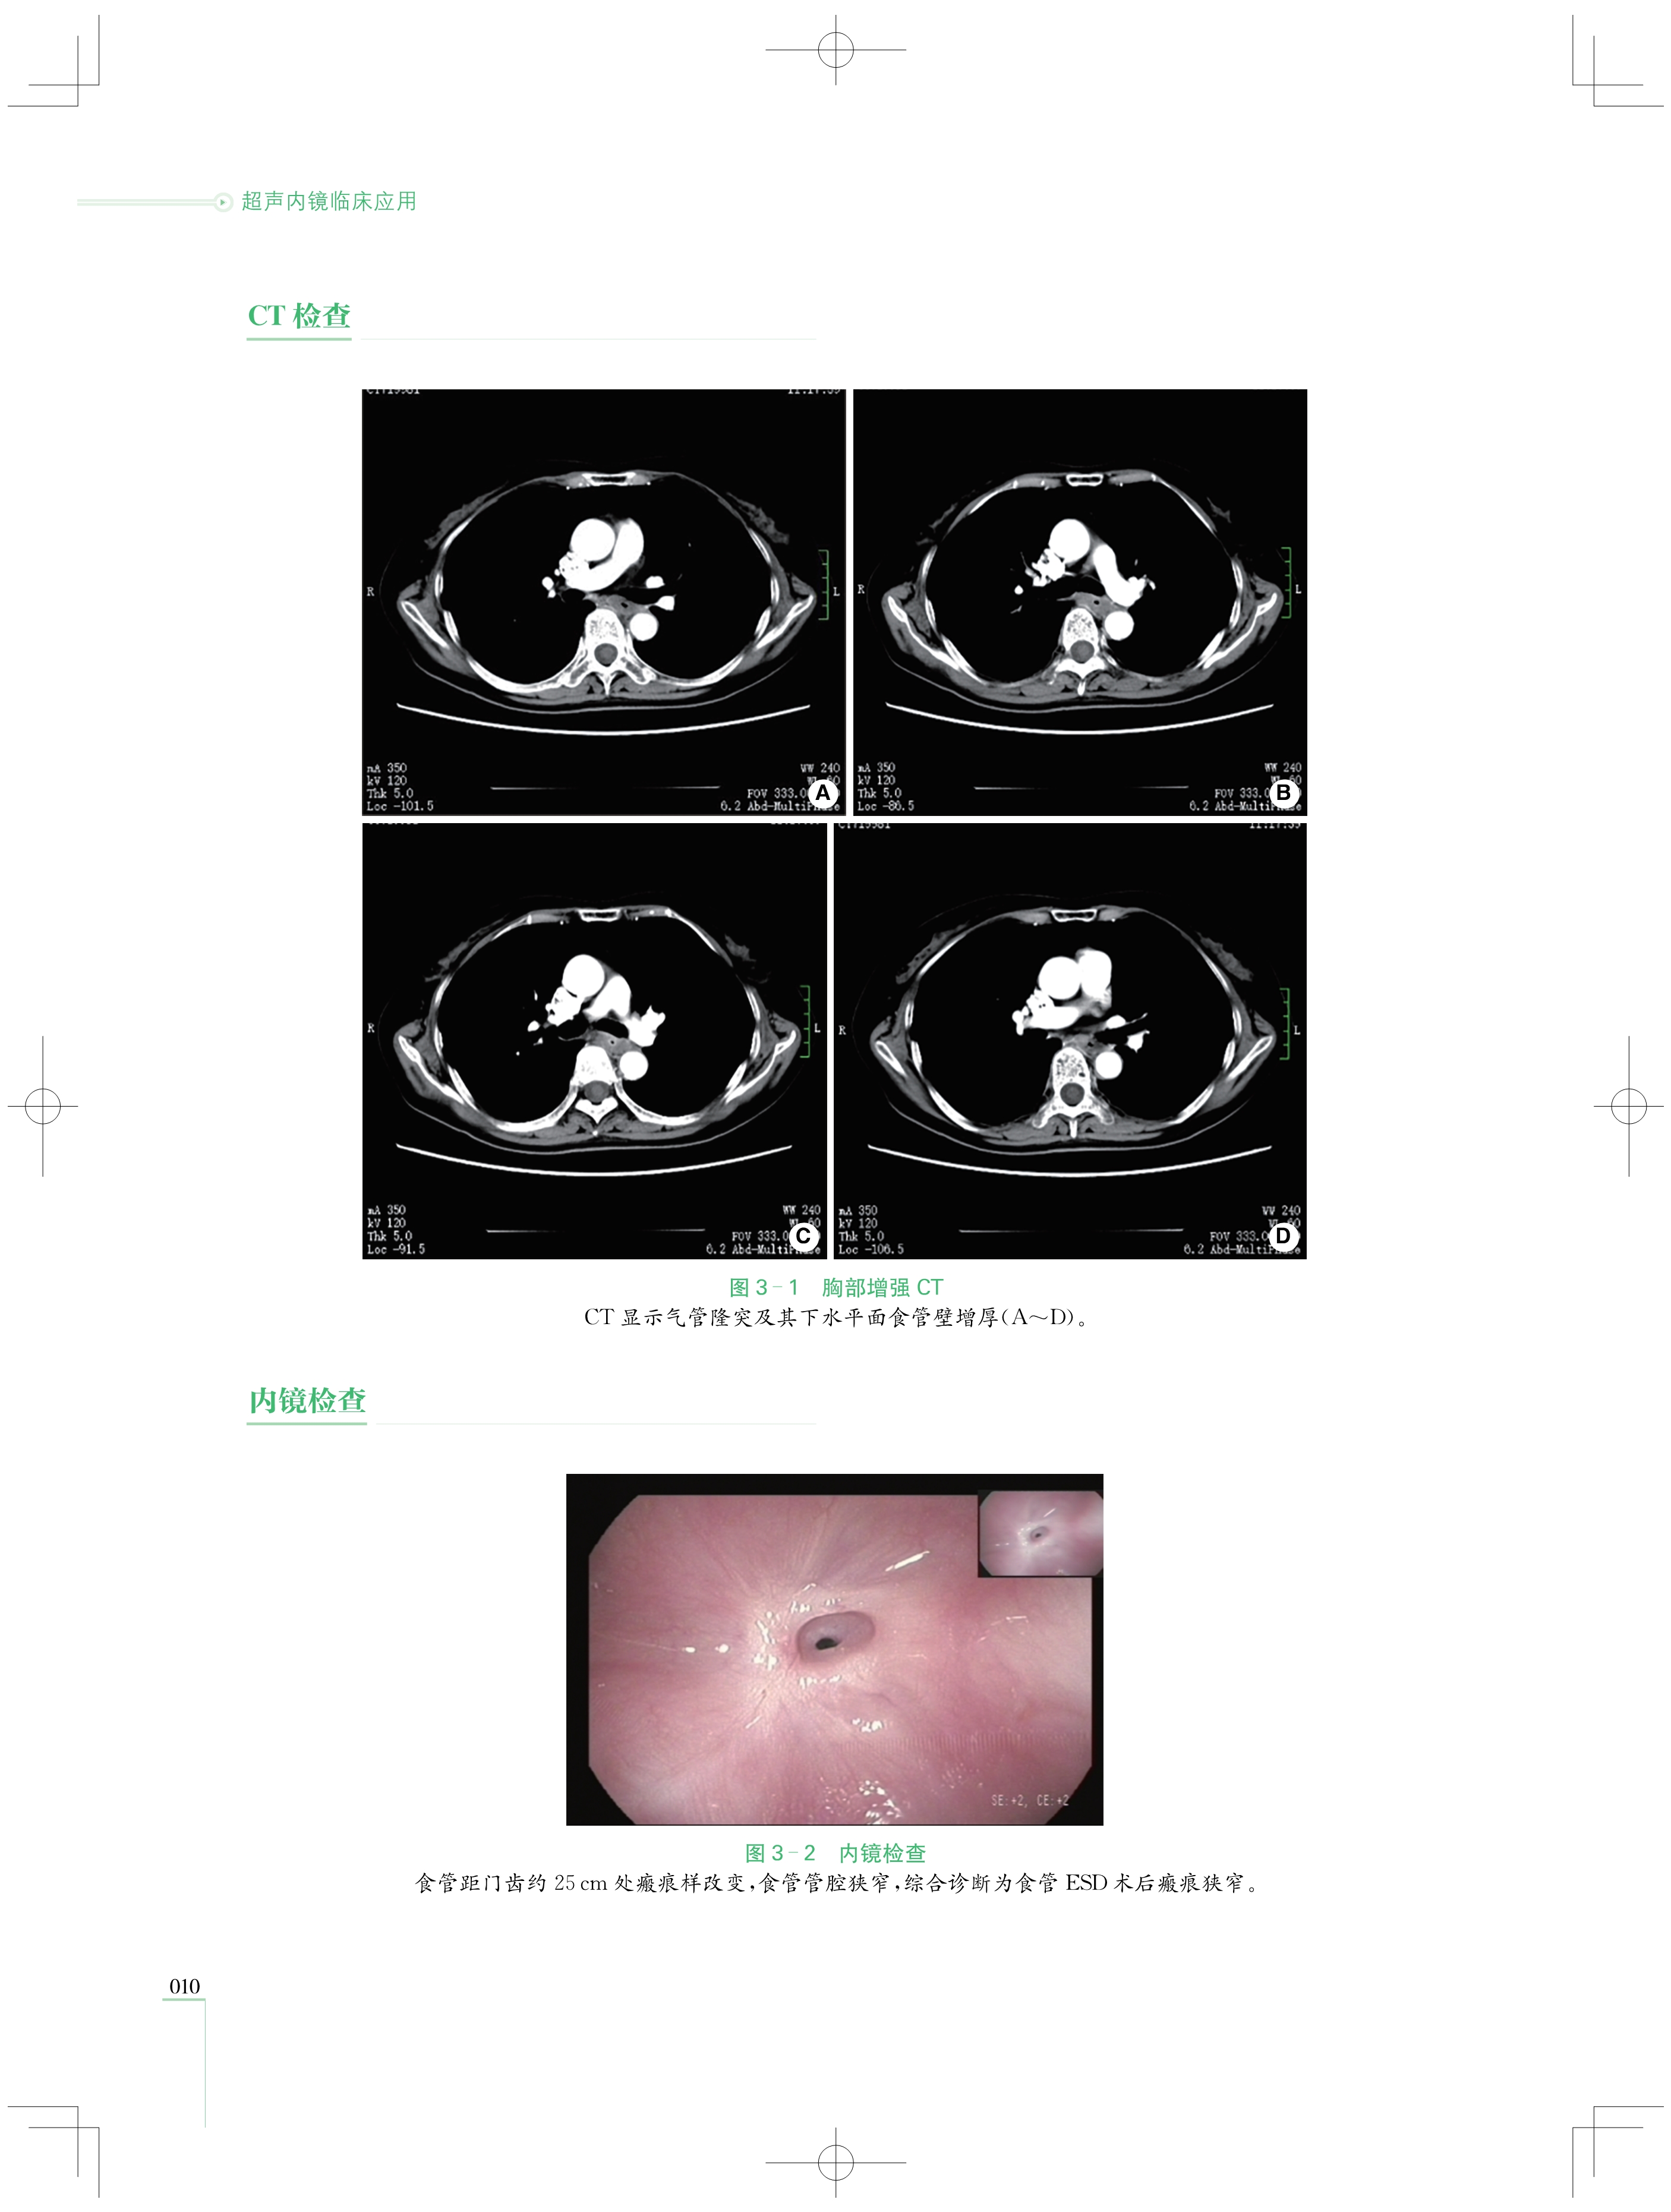

本书收集了第一届至第五届“ 中国介入性EUS视频大赛 ”的优秀获奖病例共计87例,涵盖超声微探 头及介入性超声内镜( EUS)两大领域,这些病例皆历经严格筛选,具有极高的代表性和典型性,全面覆盖了 消化系统的复杂疑难病症。从极为罕见的消化道黏膜下病变,到极易混淆的纵隔占位性疾病,每一个病例 都翔实还原了诊疗经过、超声图像与病理对照,为读者展现完整且严谨的诊断思维体系,帮助读者在复杂的 病情中抽丝剥茧,精准把握疾病本质。